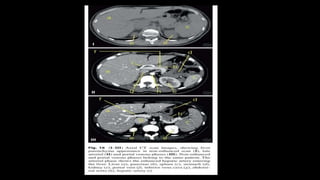

• CT liver volumetry is an essential imaging study in preoperative

assessment for living donor liver transplantation.

• Hepatic venous phase is used for CT volumetry. 6 or 8 mm slice

thickness used.

• Liver boundary is traced to exclude the surrounding structures/organs as

well as vessels and hepatic fissures, then we summate the liver area on

every single cut

• Virtual hepatectomy plane is drawn on each cut on axial images, to the

right of the middle hepatic vein in right hemihepatectomy and along

falciform ligament in left lateral segmentectomy

• Volume of all cuts is summed to get the total and lobar volume of the

liver